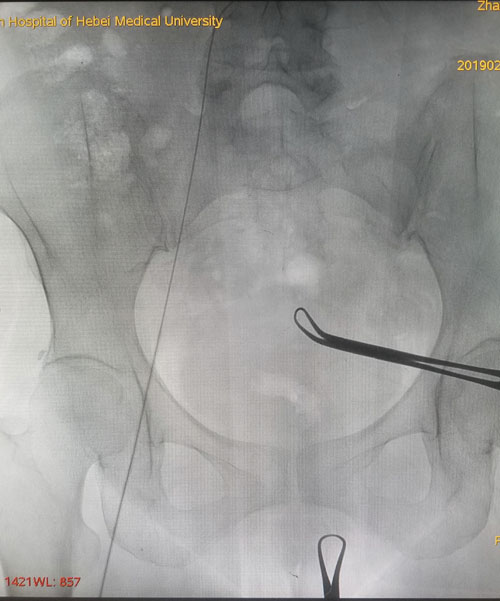

術中DSA評估導絲走形